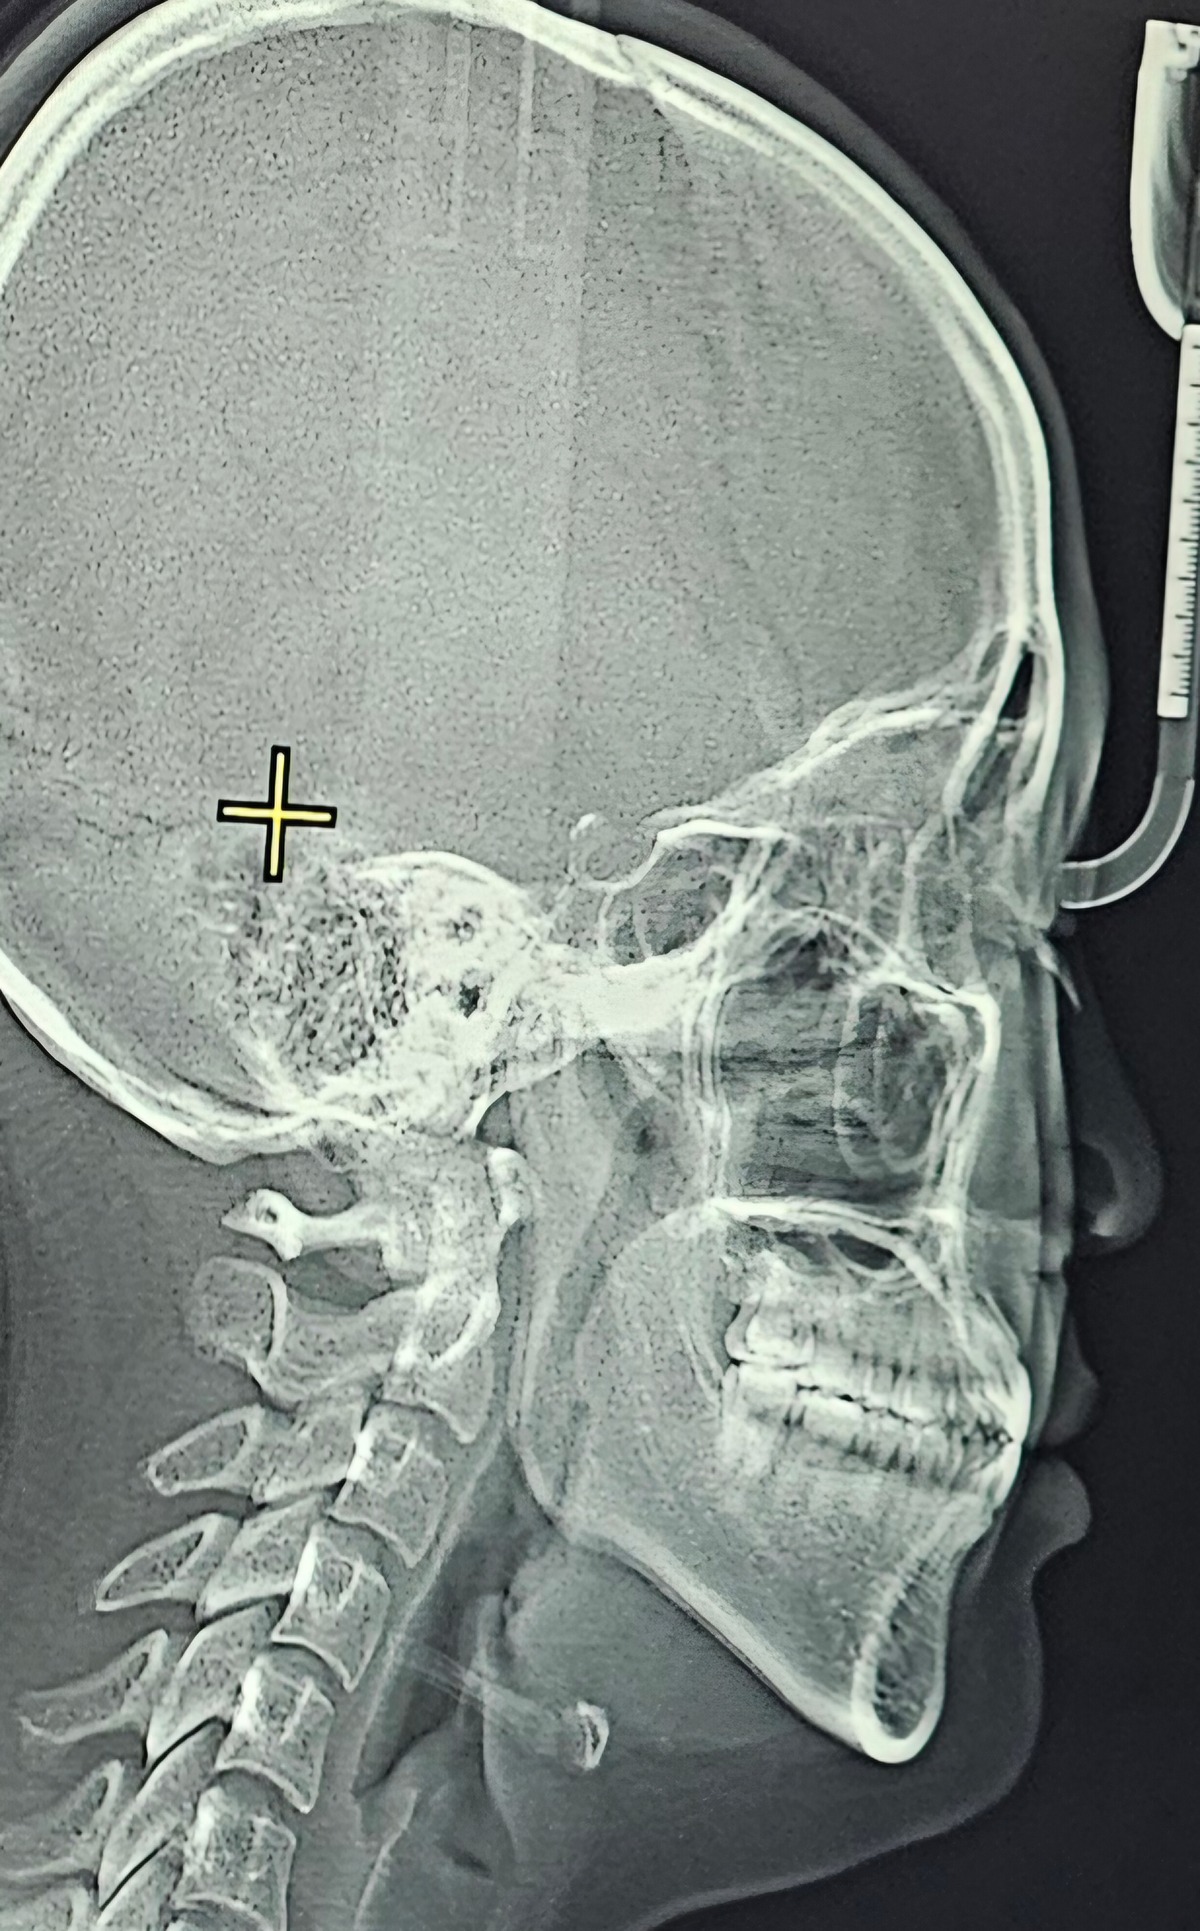

어릴때 턱 교정이랑 덧니 교정을 했었어 철길 깐건 아니구 그냥 장치를 넣었다 뺐다가 하는 그런거였고 덧니랑 턱 튀어나온건 많이 나아졌었음 지금은 26살인데 내 앞니가 딱 맞물려있고 윗니 아랫니 앞쪽 한두개가 살짝 틀어져있어 남이 볼때는 잘 모르는데 내가 혀로 만지면 좀 들어와있고 나가있고 하는 정도? 어릴때는 신경 안쓰였는데 엄마가 자기 틀어진 이가 있는데 나이들면서 틀어진 이 때문에 다른 이가 튀어나오게 됐다고 말하면서 나도 교정할까 고민을 해봤어 턱이 점점 나오는 것도 고민되기도하고 요즘 다이어트 하면서 살 열심히 빼는 중인데 교정까지 해볼까 하구ㅠㅠ

견적은 클리피씨 450에 스크류 2개 박고 1년 6개월~8개월정도래 윗니에는 평생 부착식 유지장치, 아래는 끼우는 유지장치 껴야한다했고 인비절라인은 기간 동일한데 650이야 고민이 너무 되는데 할지말지 도와줄 수 있을까!?